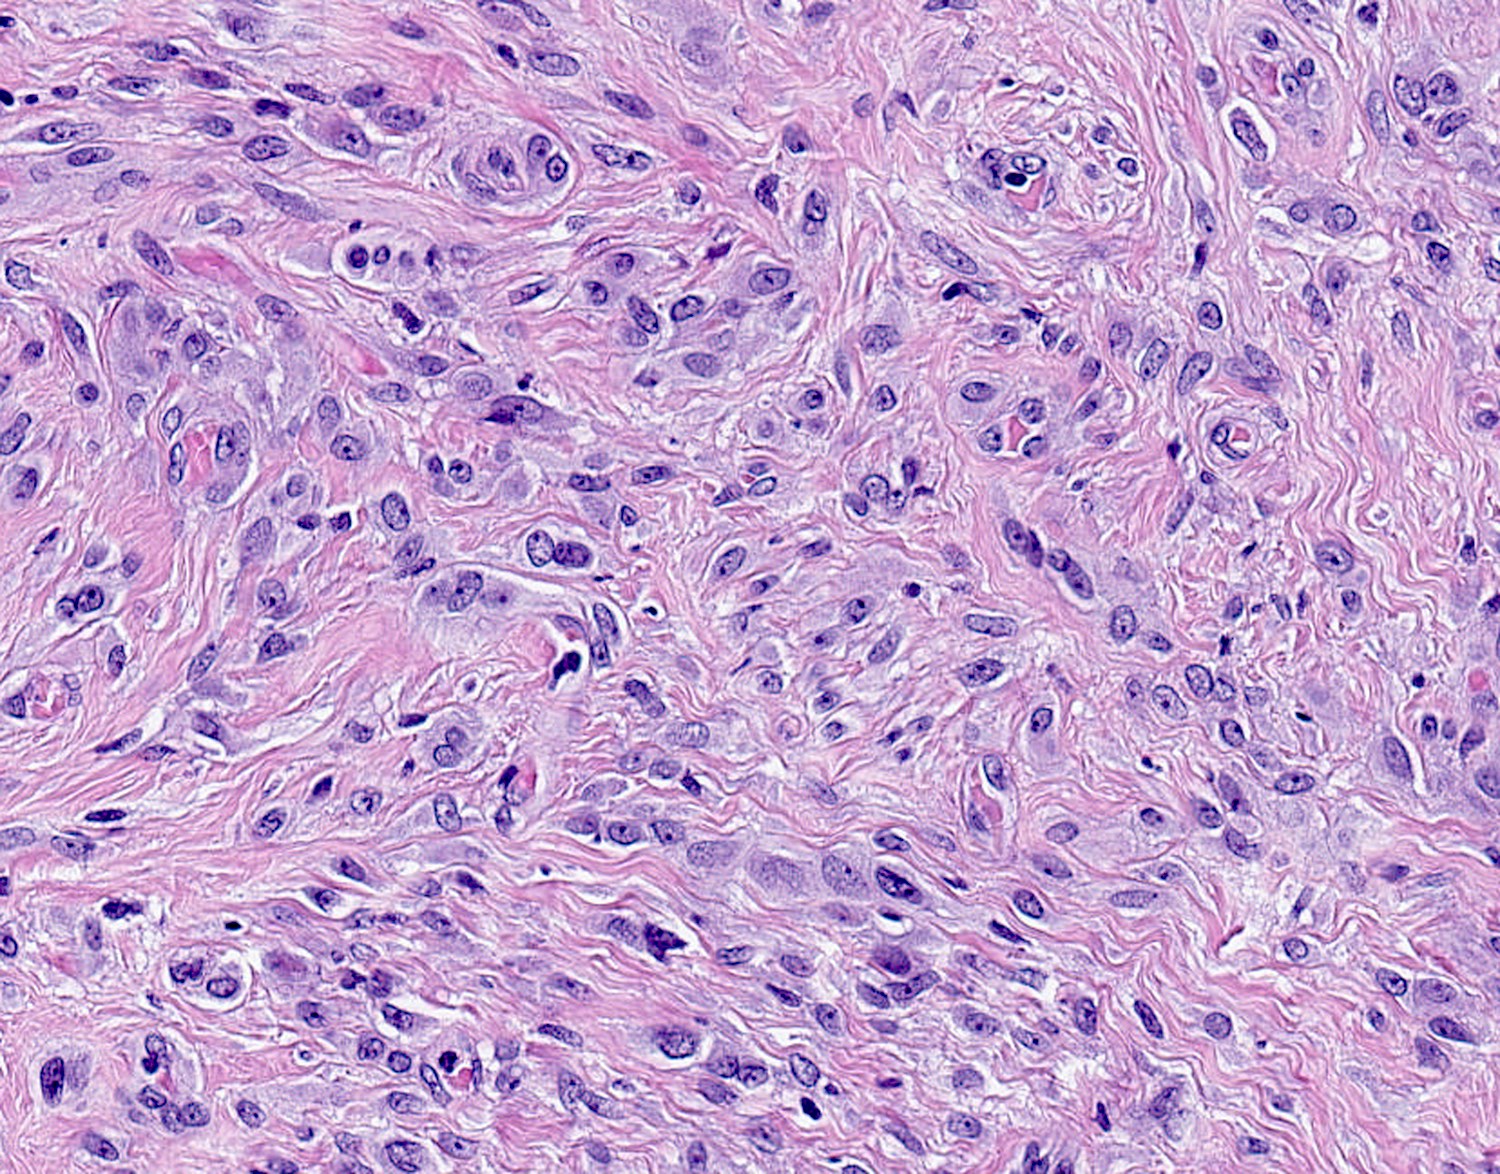

Microscopic (histologic) description

- Well circumscribed, lacks true capsule, rarely infiltrative

- Bland, uniform, short to elongated spindle cells arranged as short haphazard intersecting fascicles admixed with bands of hyalinized, brightly eosinophilic collagen and variable amounts of fat

- No more than mild nuclear atypia

- Mitoses usually absent, atypical mitoses and necrosis absent

- Mast cells common, perivascular lymphocytic infiltrates on occasion

- Focal myxoid stromal changes common

- Variants:

- Myxoid: stellate and spindle cells in abundant myxoid stroma (Histol Histopathol 2016;31:1)

- Deciduoid: large round, polygonal cells with abundant eosinophilic glassy cytoplasm, single or multiple prominent nucleoli which may be eccentrically placed, binucleation, sharp cell borders, eosinophilic intracytoplasmic inclusions (Histopathology 2008;52:652)

Microscopic (histologic) images